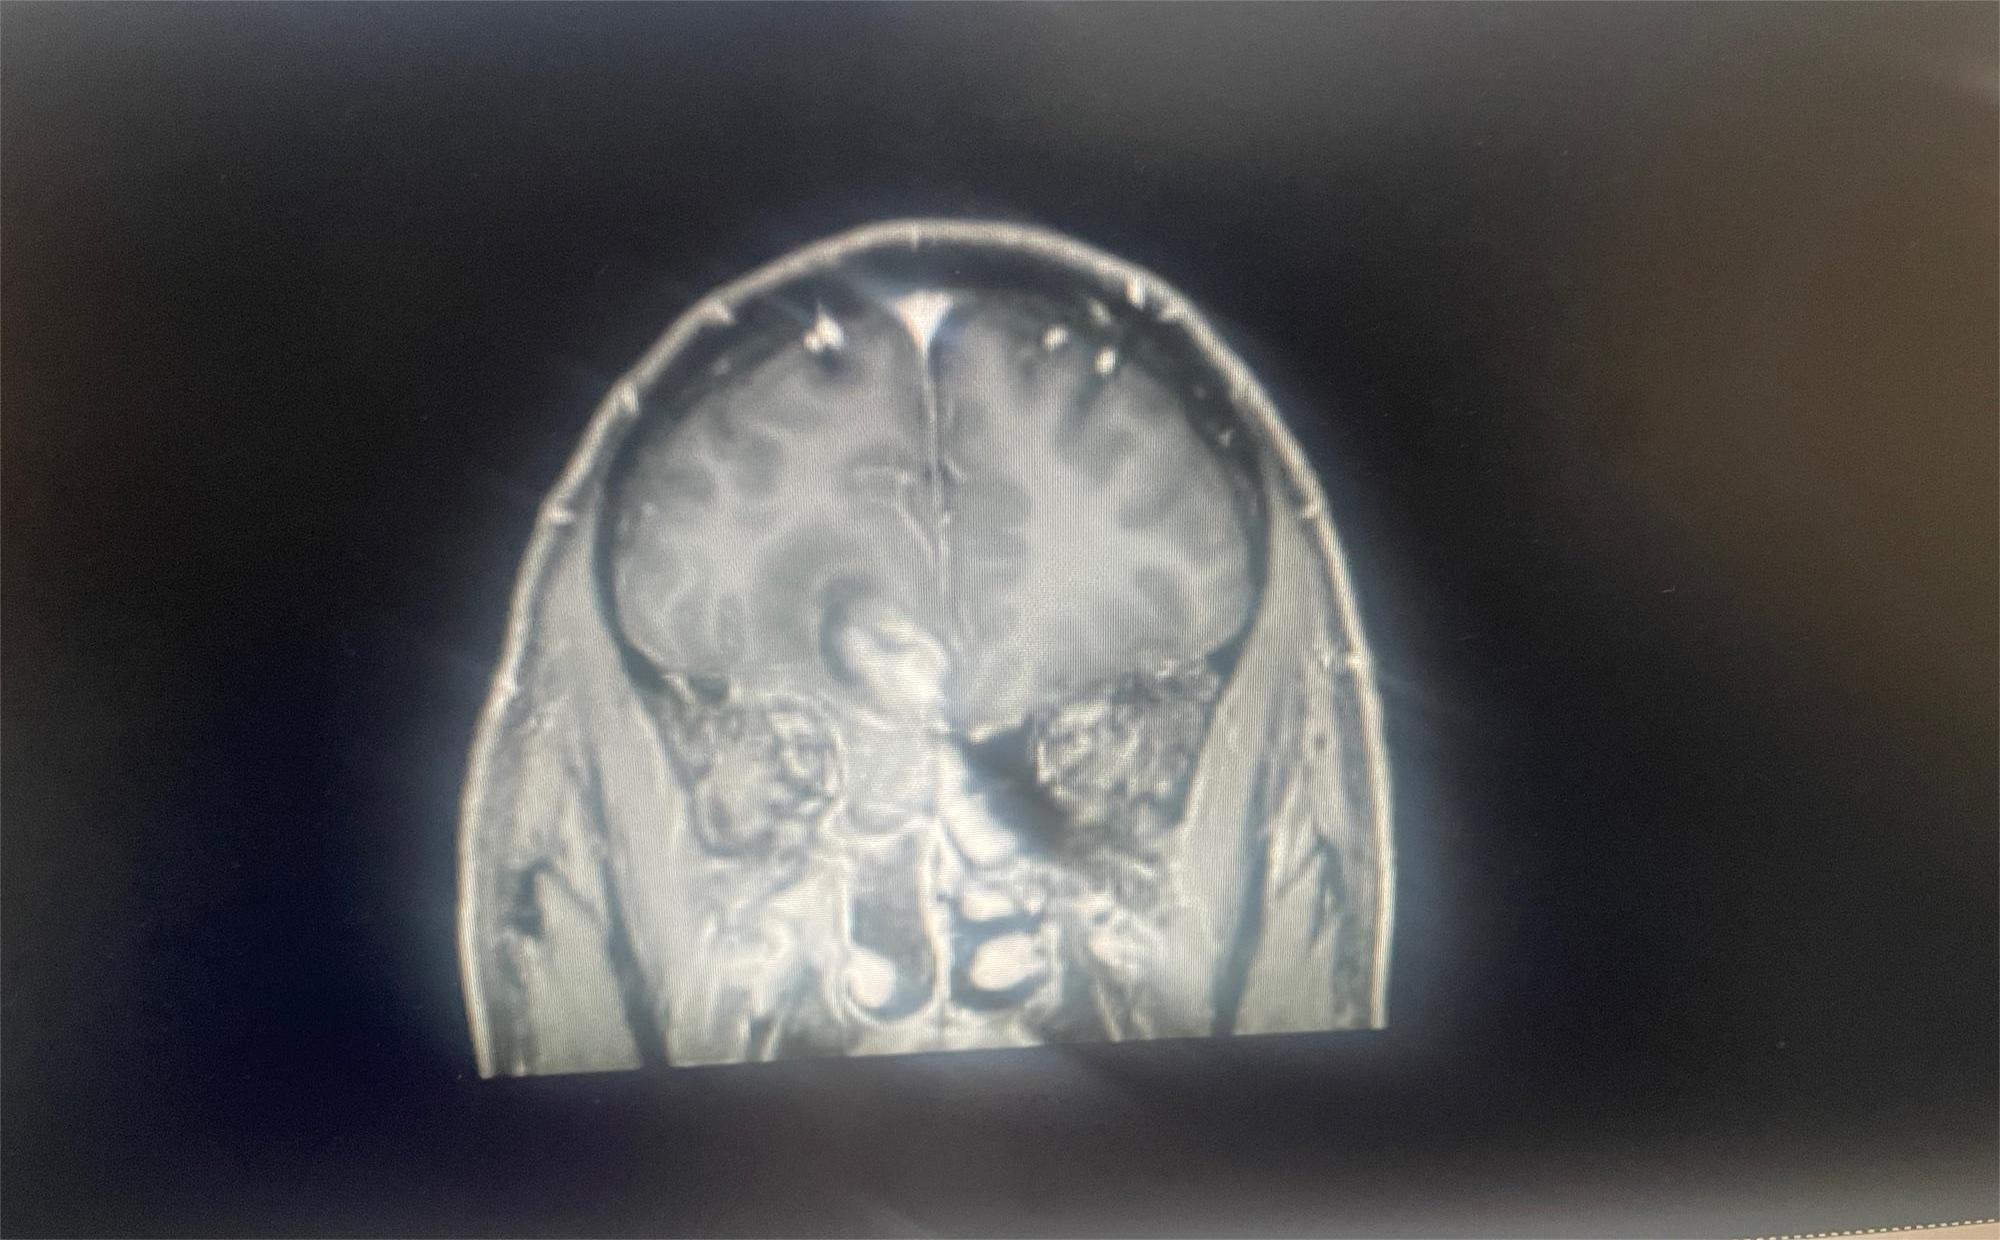

• 幻灭人海

幻灭人海  0

2023-10-19   患者家属

求助有没有比较好医院或者治疗好的方案

共1张

脑部肿瘤求助

0人关注    2个回复    862次浏览